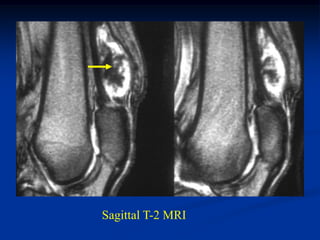

CLASSIC     Case #285         Sagittal T-1 MRI

67 year female with myxoid liposarcoma knee

Sagittal T-2 MRI

Axial T-2 MRI

CLASSIC Case #285 Sagittal T-1 MRI 67 year female with myxoid liposarcoma knee